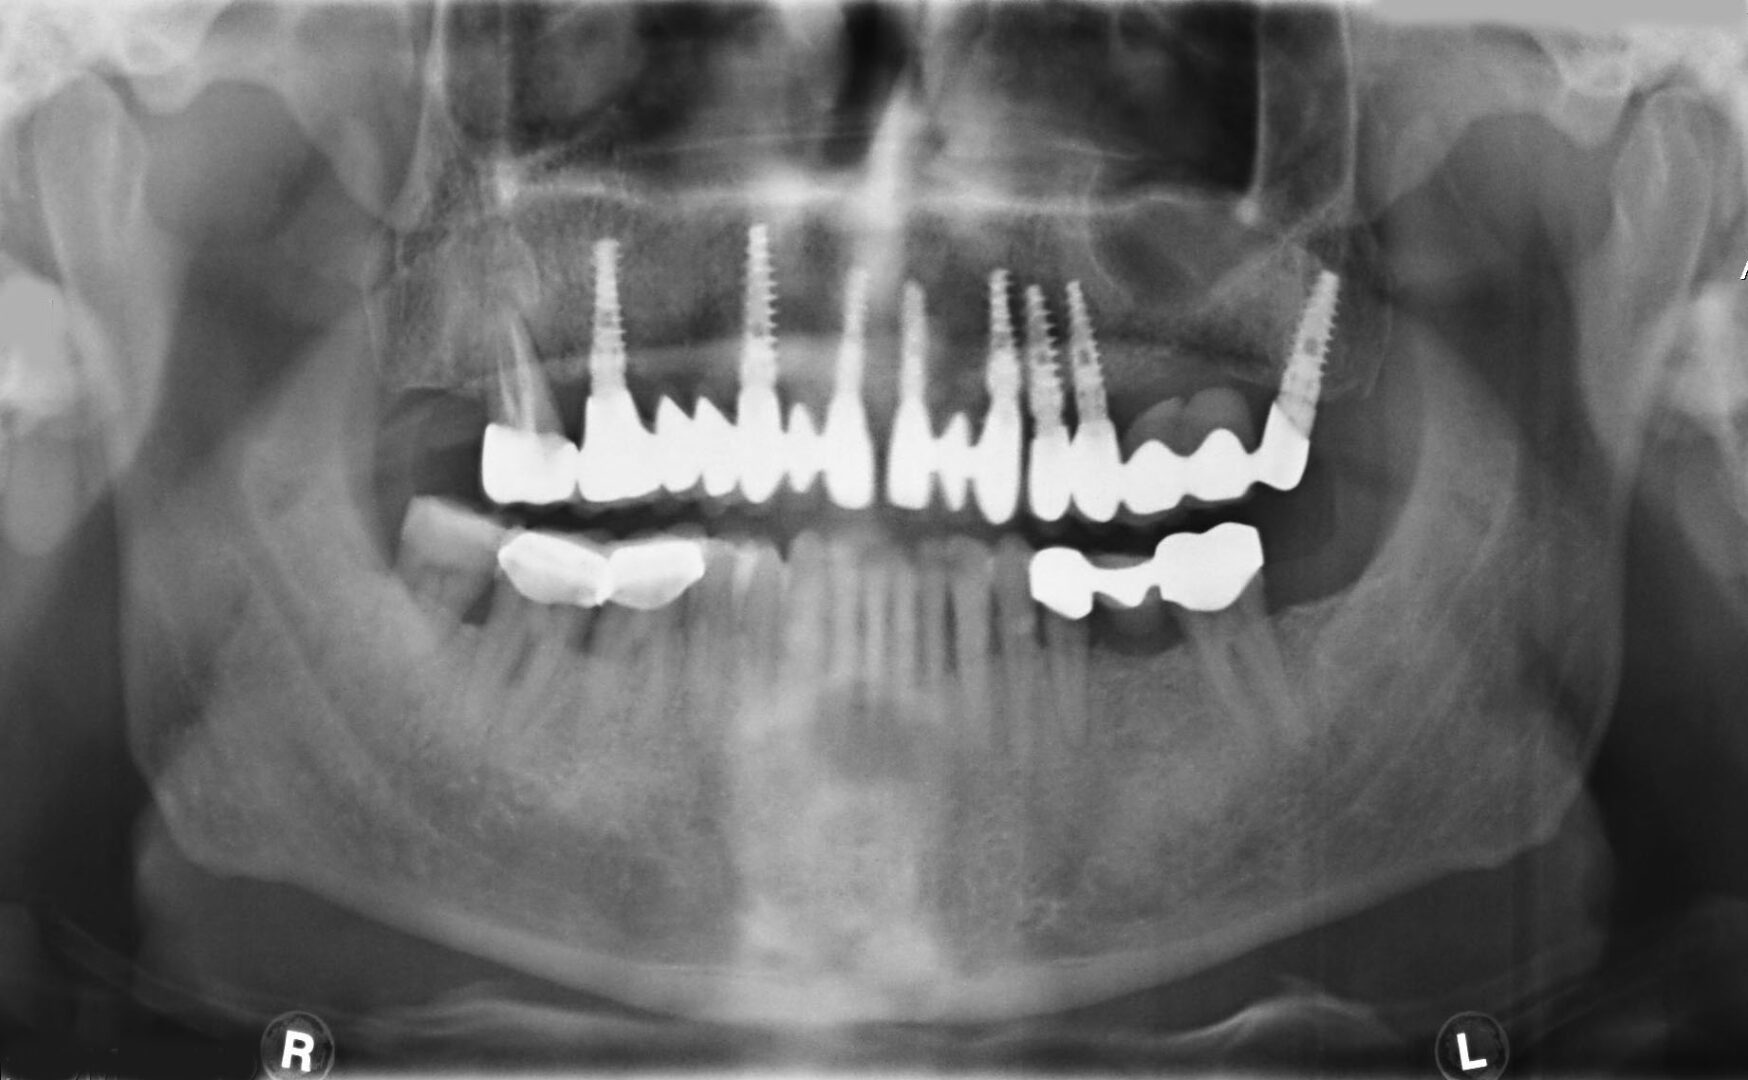

Αποτελεί και αυτή επέμβαση ρουτίνας για τους Στοματικούς και Γναθοπροσωπικούς Χειριουργούς, με αποτέλεσμα που αγγίζει σχεδόν πάντα το άριστο. Και εδώ το πιό συχνό αίτιο αποτυχίας, είναι το ίδιο όπως αναφέρθηκε πρωτύτερα για τους φρονιμίτες. Είναι πλέον γνωστό σε όλους ότι τα οδοντικά εμφυτεύματα συμβάλλουν στην αποκατάσταση της λειτουργίας της μάσησης, της κατάλληλης σύγκλισης και της διατήρησης  του οδοντικού φραγμο

Κάποιοι ασθενείς δεν προτιμούν τις κινητές οδοντοστοιχίες ως προσθετική αποκατάσταση, καθώς και άτομα μικρής ηλικίας με απώλεια δοντιών, η επιλογή των οδοντικών εμφυτευμάτων είναι η προτιμότερη λύση. Αλλά ακόμα και στους ασθενείς που έχουν προσαρμοστεί με τις ολικές οδοντοστοιχίες, αλλά δυσανασχετούν με την κινητικότητα αυτών πάλι τα οδοντικά εμφυτεύματα δίνουν καθοριστική λύση.